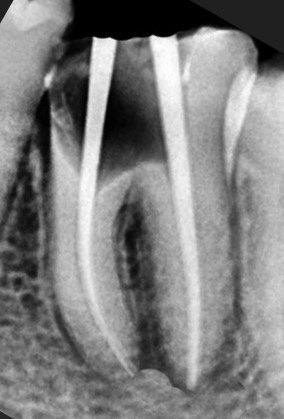

Before

After

Lower Molar

Complex Case

Complex Molar Rescue

High-risk lower molar with severe infection treated successfully using advanced endodontic techniques.

High-risk case managed

Infection fully controlled

Long-term tooth stability